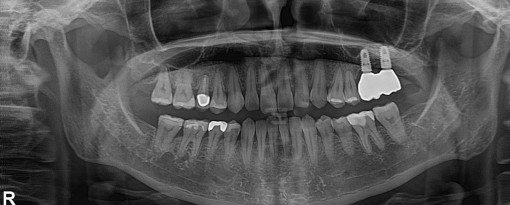

当院では、世界的歯科機器メーカー「デンツプライシロナ社」が開発した口腔内スキャナー『プライムスキャン(PrimeScan)』を導入しています。従来の印象材を使用しない“デジタル印象”により、精度・快適性・スピードすべてにおいて次世代のインプラント治療を提供しています。

CT×IOSでインプラントを入れる位置・深さ・角度まで立体的に設計し、ズレの少ない安全な治療計画が可能になります。